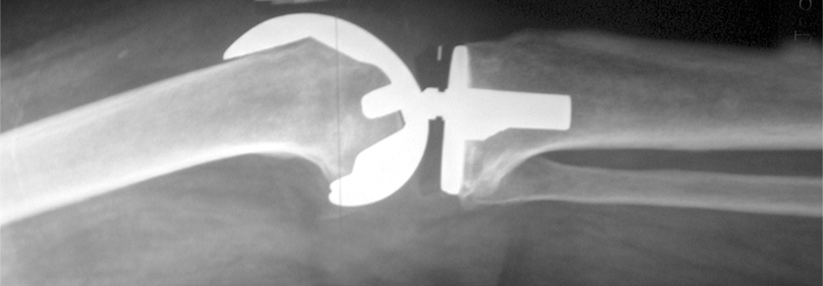

Tückische Folgen der Gelenkersatz-Operationen: Mit der Zahl der Revisionseingriffe steigt auch die Zahl der Infektionen und die Mortalität.